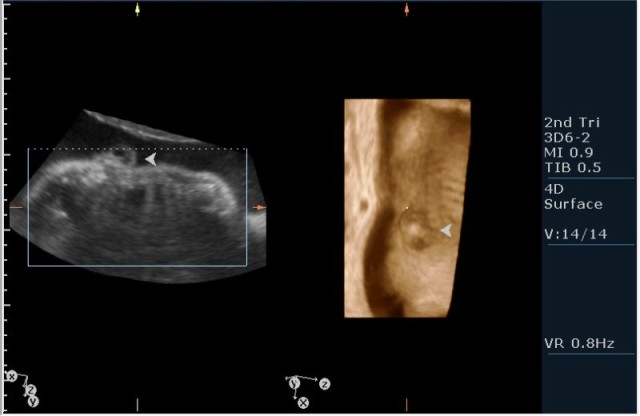

3.наличие дорсально расположенного содержимого спинномозгового канала(на сонограмме №7 видны мозговые оболочки).Это описывается как менингоцеле.

Ваш аппарат имеет режим объемной визуализации 3D/4D.Для постановки диагноза Вам в данном случае лучше было использовать не режим поверхностной реконструкции "Surface",а режим для визуализации скелета "Skeleton".В таком случае дефекты позвоночника будут видны отчетливее.

На сонограммах головы плода визуализаируется гифдроцефалия, патогенетически связанная со спинномозговой грыжей (менингомиелоцеле) представленная в 2D и 3D режимах. В режиме Skeleton не удалось получить "картинку презентационного качества", плод начал сильно вертется; но рекоммендация очень грамотная :idea: , спасибо за ваш пост!